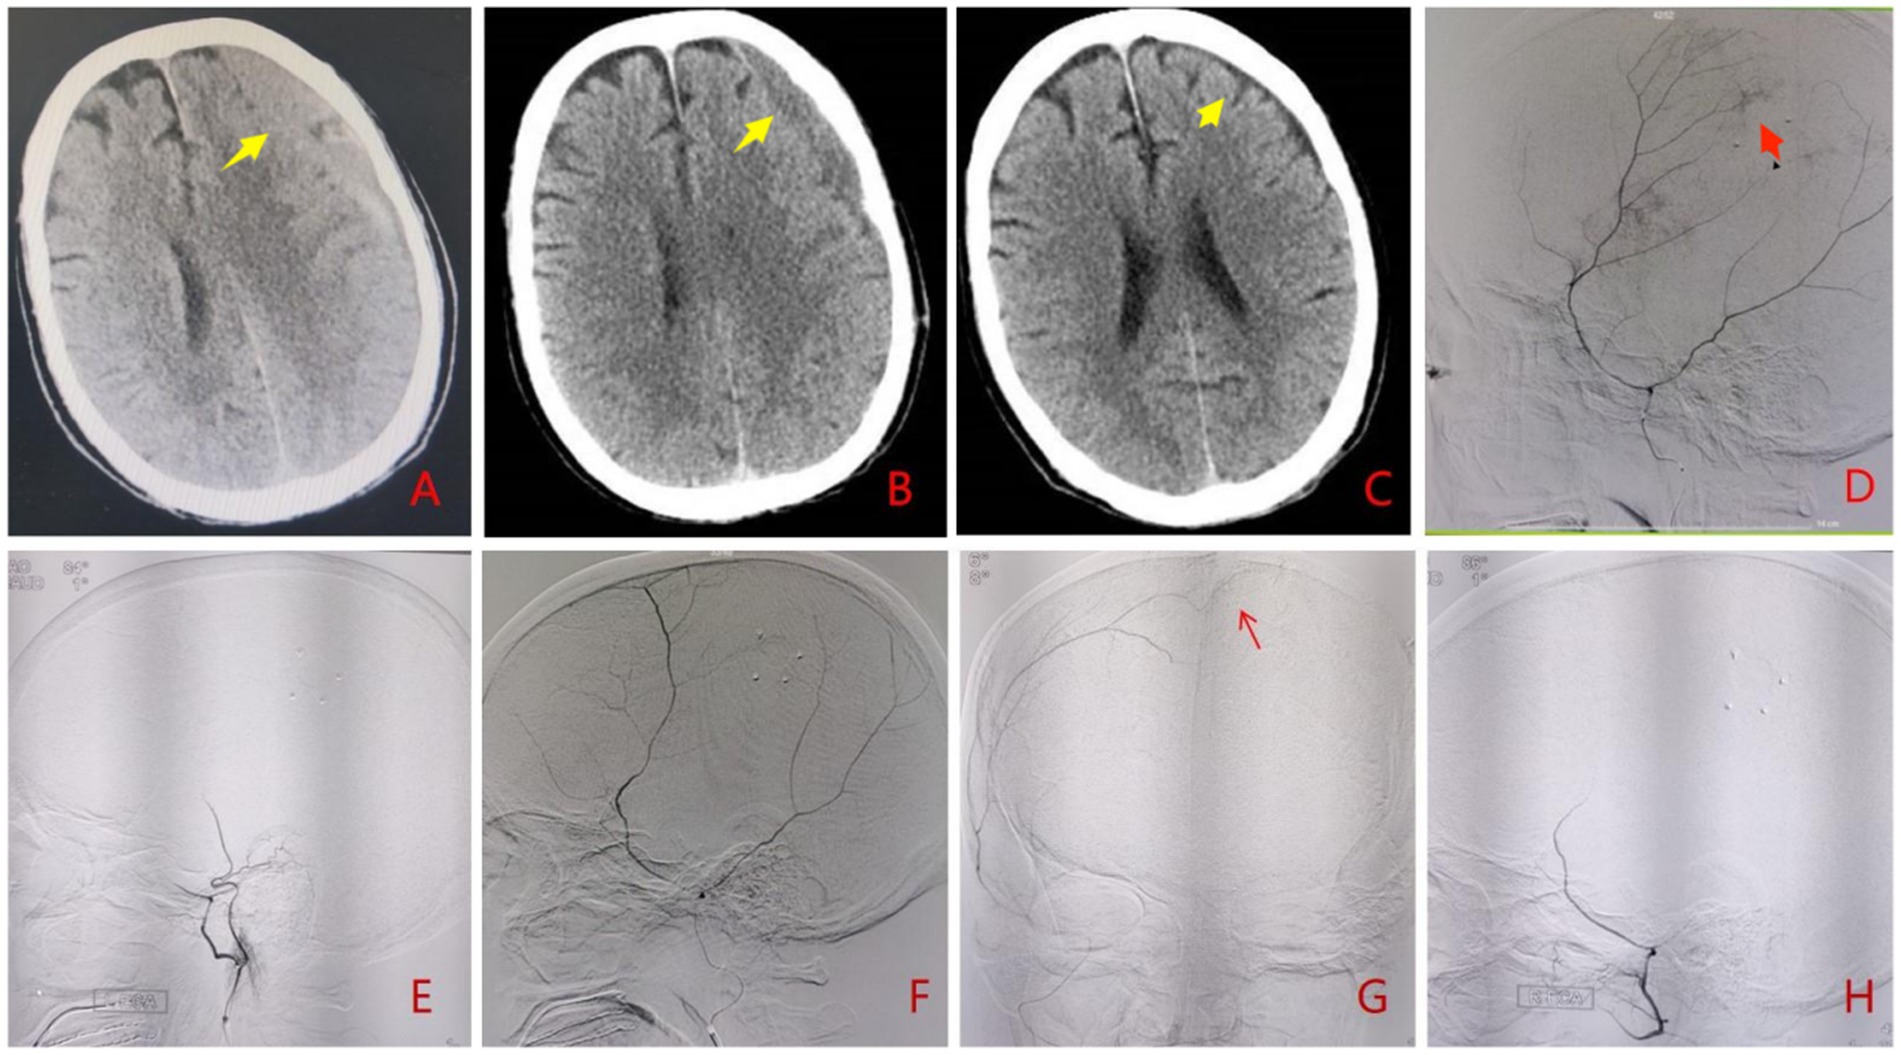

Figure 2. A 73-year-old male patient presented with headache and recurrence of left CSDH after burr hole drainage. (A) Preoperative cranial CT showed recurrence of left CSDH (yellow arrow). (B) Cranial CT at 1 month postoperatively showed obvious absorption of subdural hematoma (yellow arrow). (C) Cranial CT at 4 months postoperatively showed subdural hematoma had disappeared with residual subdural effusion (yellow arrow). (D) Superselective angiography of the left MMA before interventional procedure showed thickening of distal branches and cotton wool-like staining (red arrow); (E,H) There was no contrast agent filling (black arrow) at the distal end of bilateral MMA branches postoperatively; (F,G) Superselective angiography of the right MMA before interventional procedure showed thickening of distal branches and crossing thed midline to form compensatory anastomoses (red arrow).

Procedure

Under local anesthesia, selective angiography of the middle meningeal artery (MMA) branches demonstrated hypertrophy of the affected distal vessels, along with multiple areas of cotton-wool-like staining. Additionally, branches from the contralateral middle meningeal artery were observed crossing thed midline to form compensatory anastomoses (Figures 2D,F,G). Subsequent embolization of bilateral distal MMA branches was performed using 100–300 μm Embosphere microspheres (Figures 1E,H). Post-embolization imaging confirmed complete occlusion of the distal MMA branches.

Follow-up

Cranial CT scans at 4 months post-procedure revealed complete hematoma resolution (Figures 2B,C). The patient achieved full symptomatic recovery with an mRS score of 0.